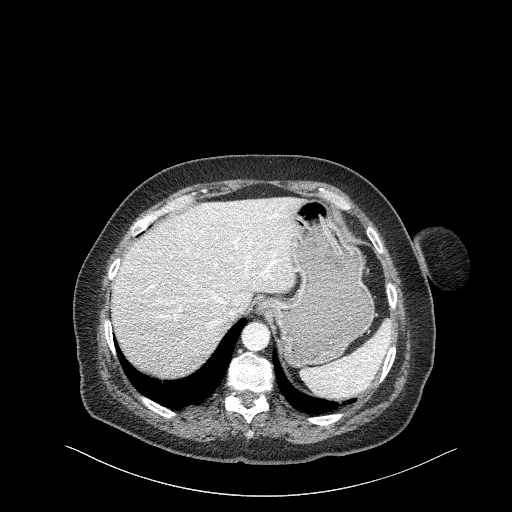

Generated VENOUS CT scan (A→B translation)

Full window (WL 1023.5, WW 4095 β†’ Low βˆ’1024, High +3071)

Actual HU range: [-1024.0, 1032.9]